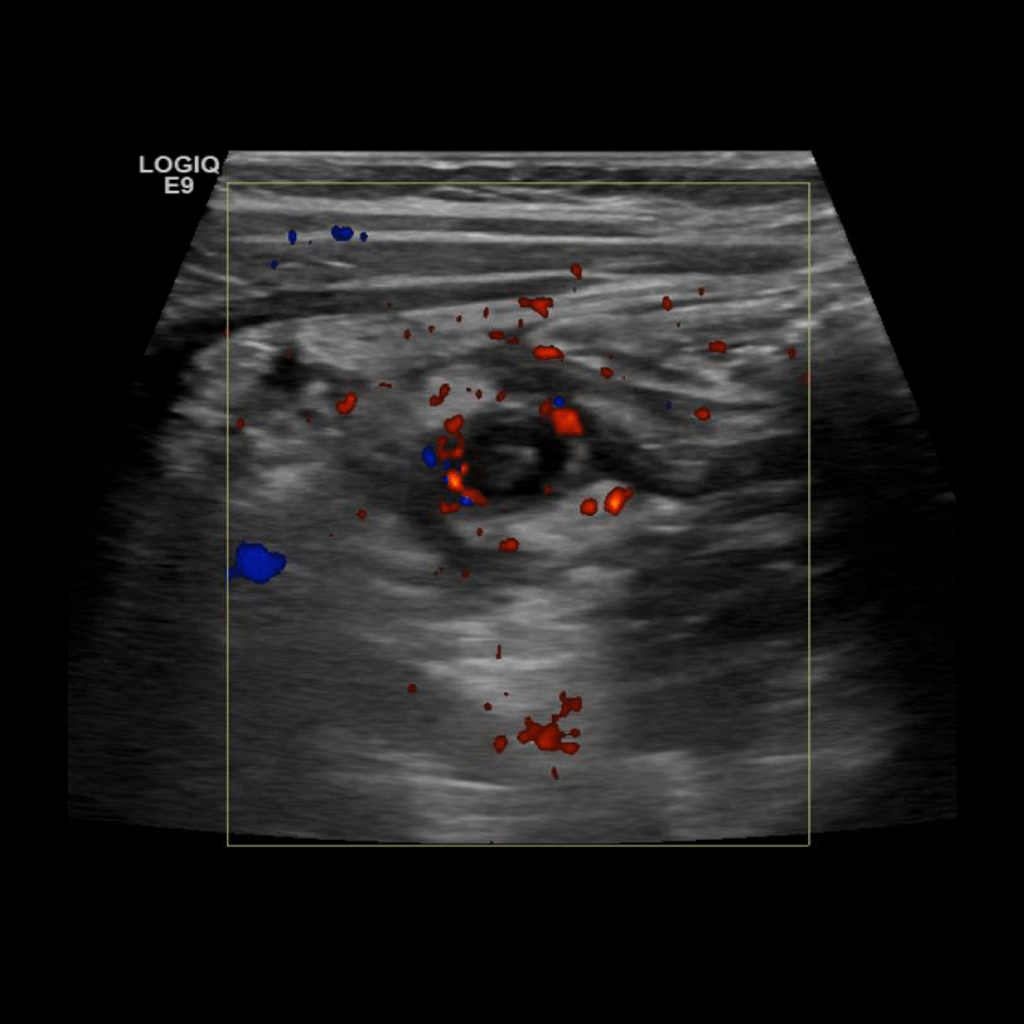

Appendicitis 5

1.5 cm appendicitis with hyperemia.